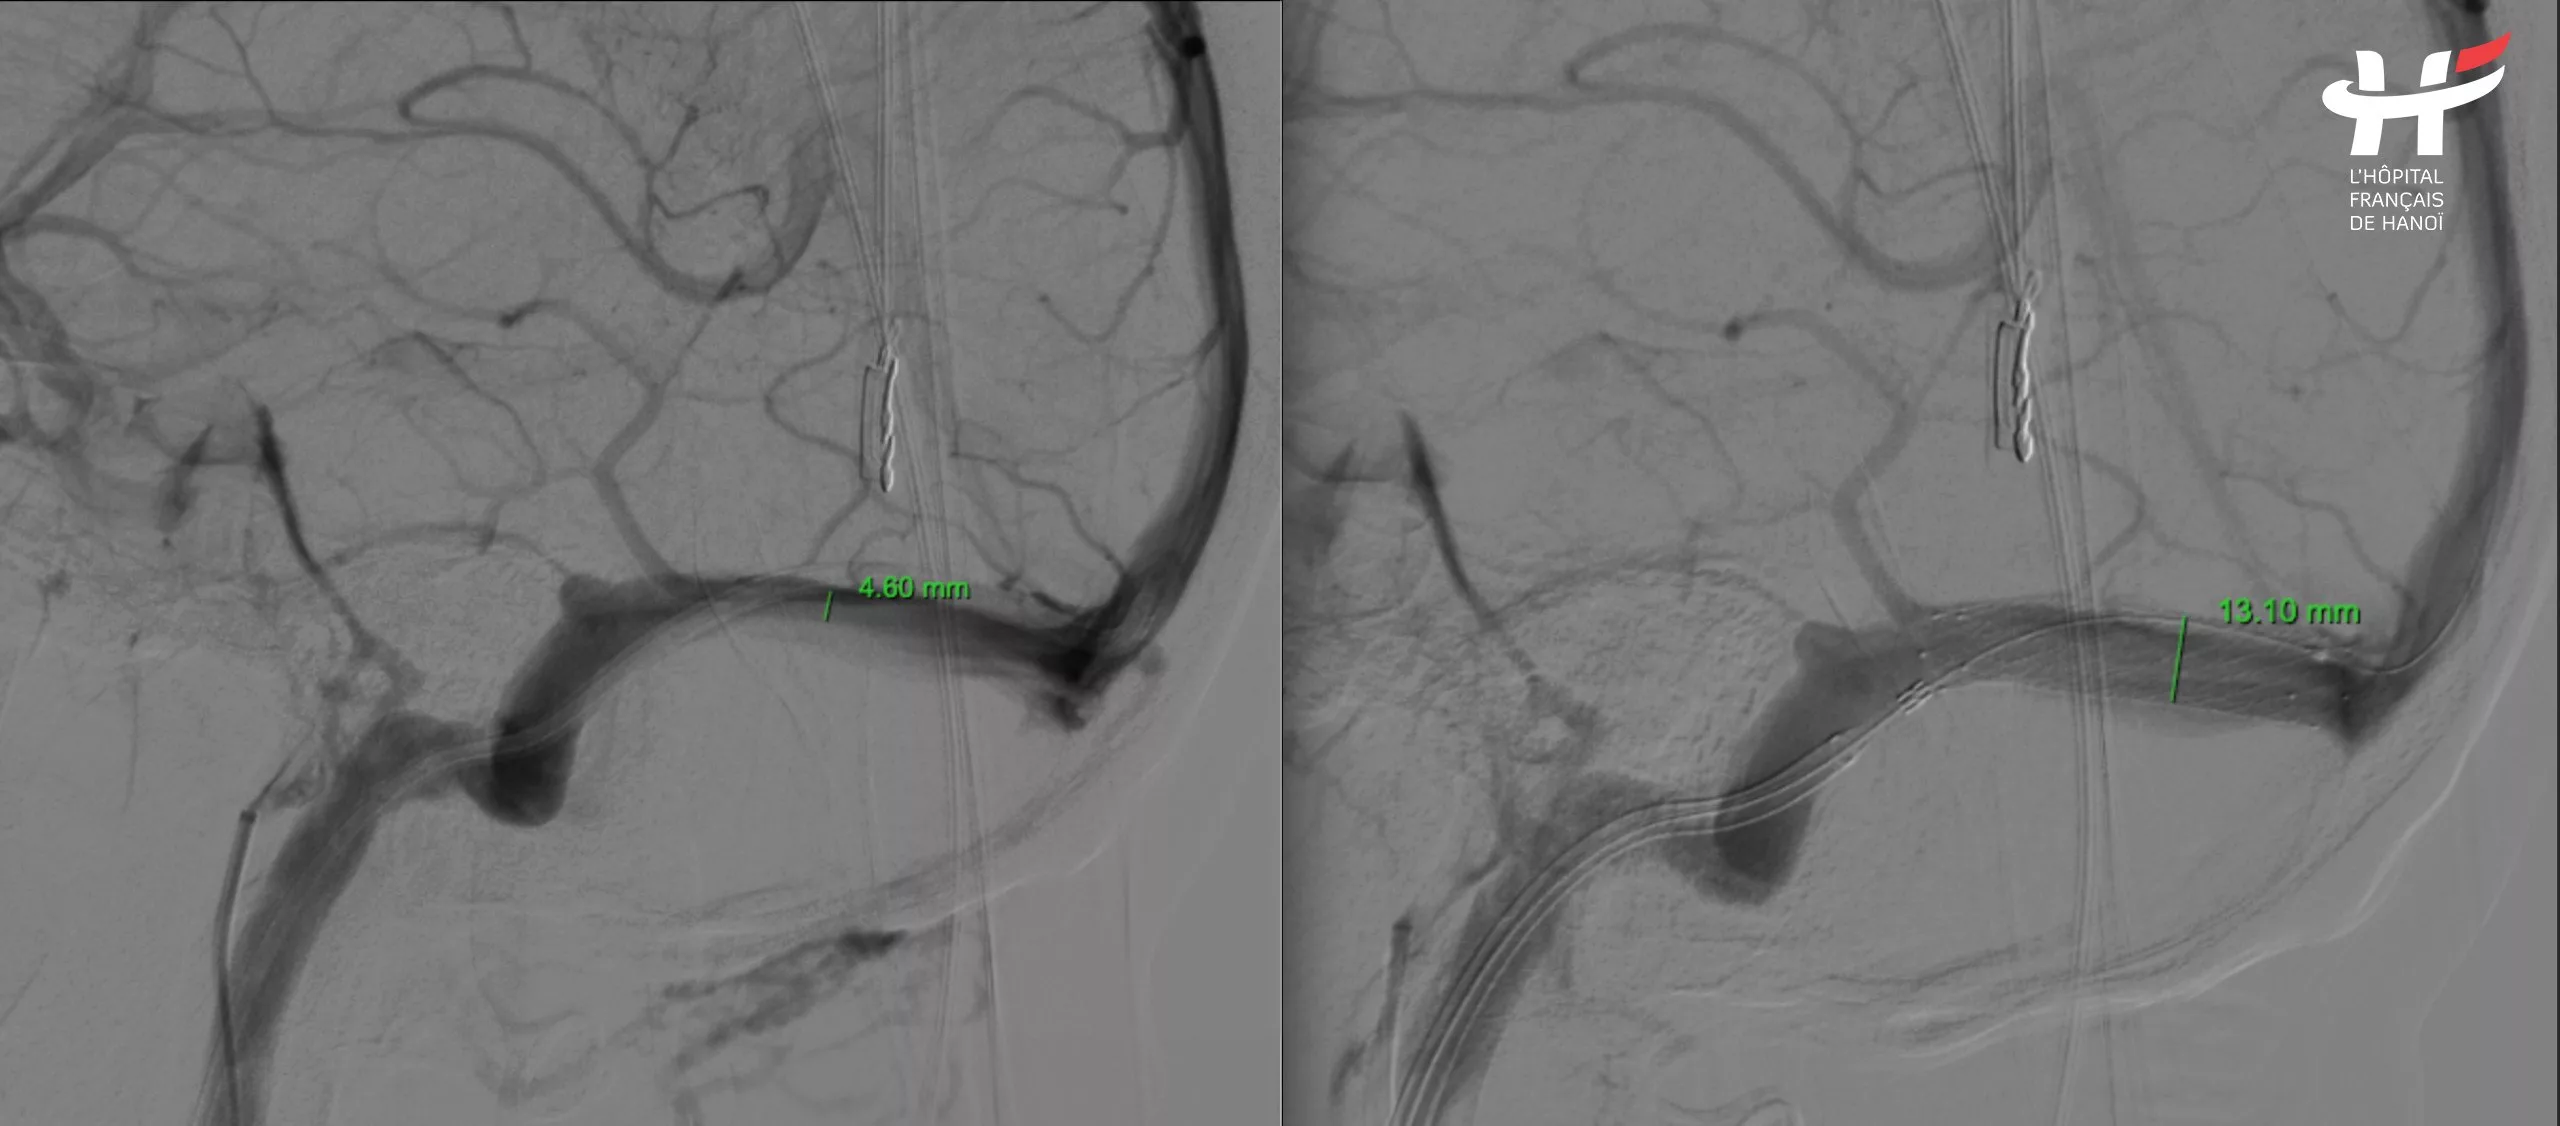

After consulting with these vascular interventional radiologists experts, they could confirm that the patient had a severe right transverse sinus stenosis. This abnormality could explain all the patient’s suffering over the past years. And it was a treatable disease.

Dr. Nguyễn Ngọc Cương, a specialist in cerebral vascular intervention, said: “Cerebral vein stenosis is a rare condition globally. Imagine a vein as a pipeline, similar to a water hose. When the hose is narrowed, the flow speeds up and jets further. Initially, the cerebral vein is as wide as usual, but over time, as the condition develops, the vein narrows, functioning like the water hose. When blood flows through the narrowed section of the vein, its speed increases rapidly.”

“The patient’s vein narrowing is located right next to the ear, causing the blood flow to exert significant pressure as it passes through. This explains why the patient hears a whooshing sound in her ear. Additionally, this vein narrowing prevents blood from being efficiently transported back to the heart, causing it to pool in the brain, which increases intracranial pressure and leads to the chronic headaches the patient experienced. The situation worsened over time as she endured both the tinnitus and headaches for 14 years.”

After a thorough discussion, the experts decided to place a stent in the patient’s right transverse sinus to clear the obstruction and restore normal blood flow. While arterial stenting is a common procedure for many conditions, venous stenting, particularly within the brain, is extremely rare. Successfully diagnosing the condition was challenging, and the intervention itself was equally difficult.

The intervention involved two main approaches. The first approach was the arterial route. They accessed the artery through the femoral artery, navigating up to the cerebral artery to precisely locate the stenosis. The second approach was the venous route. Simultaneously, they made an entry through the jugular vein in the neck, advancing the catheter up to the brain vein to place the stent.